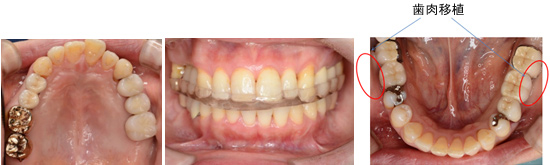

GBR(骨造成) サイナスリフト 歯肉移植 エムドゲインによる再生療法などをおこないインプラントは必要最小限で、患者さんの希望のできるだけ歯の保存ができました。

50代 女性

治療内容 歯周治療 再生療法 歯肉移植

インプラント治療 サイナスリフト 垂直的骨造成

治療後